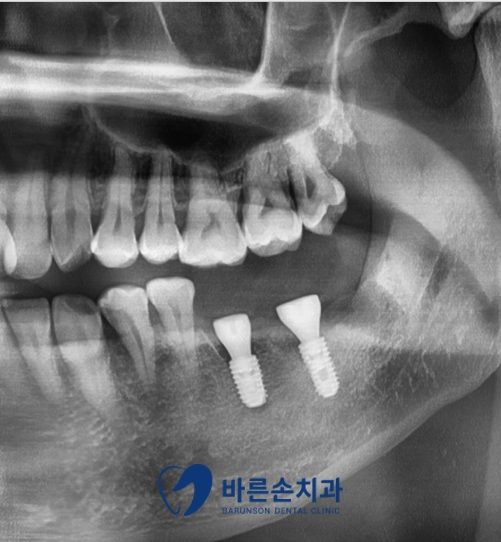

안녕하세요 <의정부 바른손치과> 입니다 오늘 소개드릴 내용은 오랫동안 방치된 치아의 발치 및 임플란트 치료에 대해서 알아보겠습니다 오늘 보실 환자분께서는 오랫동안 치과에 대한 두려움으로 인해 미루던 치료를 위해 저희 치과가 안 아프게 치료한다는 소문을 듣고 내원해 주셨다고 하시네요^^ 그럼 환자분의 사진 먼저 보도록 하겠습니다! 정확한 진단을 위해 파노라마 촬영을 같이 진행하였습니다 보시는 것과 오랜 시간 치과치료를 미루고 방치된 만큼 치아가 많이 상해 있는 게 보이네요..! 환자분의 불편감 해소를 위해 빠르고 정확한 진단으로 치료를 진행하기로 하였습니다! 진단 및 치료 계획 ■1번 치아 : 심한 우식으로 인해 치아가 손실되어 치아 뿌리만 남음 – 발치 후 임플란트 ■2번 치아 : 교합면 우식 및 사랑니로 인해 인접면 우식 및 치조골 손실 – 발치 후 임플란트 ■3번 치아 : 사랑니 우식 – 발치 충치로 인해 많이 손상되어 있던 1,2번 치아는 발치 및 임플란트, 3번 치아였던 사랑니는 발치를 하였습니다 발치 및 수술 후 파노라마와 3D-CT 확인 결과 안정적인 위치에 식립된 임플란트와 발치도 잔존 치아나 신경 손상 없이 깨끗하게 진행된 것을 알 수 있습니다^^ 치료 전후 사진입니다 처음 내원 당시와는 확연하게 다른 구강 내 사진을 볼 수 있습니다 손상되었던 치아들의 발치 후 임플란트 진행으로 전보다 훨씬 더 튼튼하고 깨끗하게 변화되었네요^^ 무엇보다도 치과에 대한 두려움이 많으셨던 환자분이셨는데 저희 치과를 믿고 진행해 주신 것에 깊은 감사드립니다^^ 저희 <바른손치과>에서는 환자분들의 불편감을 최소로 하는 진료를 우선으로 생각하기에 편안하게 내원해 주세요^^ 감사합니다^^ |